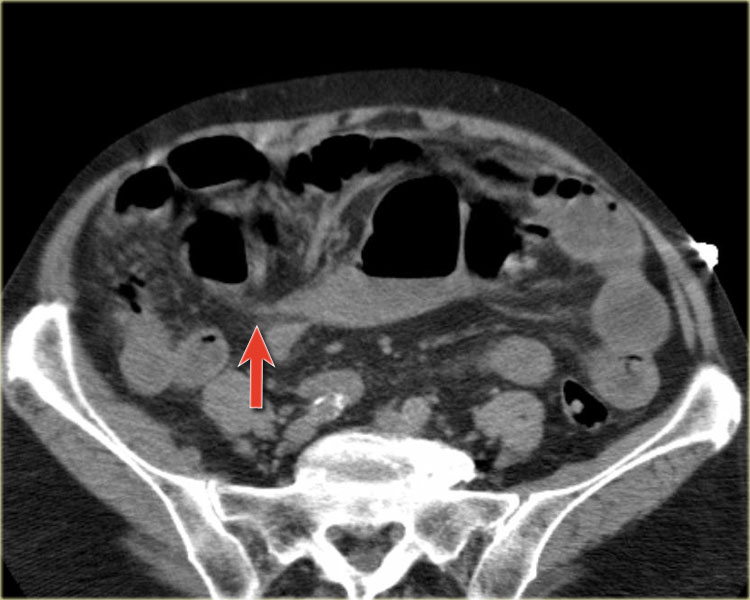

Tắc ruột dạng quai kín với các quai ruột giãn xếp theo hình nan hoa. Có dày thành ruột và phù nề mạc treo gợi ý thiếu máu cục bộ

Một hình ảnh quan trọng khác của tắc ruột dạng quai kín là các quai ruột non giãn xếp theo hình nan hoa với các mạch máu mạc treo hội tụ về một điểm trung tâm.

Hình ảnh này hầu như luôn do xoắn ruột non gây ra.

Các dấu hiệu thiếu máu cục bộ trong tắc ruột dạng quai kín tương tự như ở bệnh nhân thiếu máu mạc treo do các nguyên nhân khác:

- dày thành ruột

- phù nề mạc treo

- cổ trướng

- sự ngấm thuốc của thành ruột trong thiếu máu cục bộ có thể bình thường, tăng hoặc giảm.

Ca lâm sàng bên trái cho thấy một bệnh nhân khác bị tắc ruột dạng quai kín.

Mặc dù các mạch máu ngấm thuốc tốt, nhưng dường như thành ruột không ngấm thuốc.

Các dấu hiệu thiếu máu cục bộ khác trong ca này bao gồm phù nề mạc treo và dày thành ruột.

Ruột bị nhồi máu được phát hiện trong quá trình phẫu thuật.

Nếu quai kín dài hơn và định hướng vuông góc với mặt phẳng cắt, chúng ta sẽ thấy một cụm quai ruột như trong ca lâm sàng bên trái.

Đôi khi điều này khó nhận biết chỉ trên các lát cắt ngang và các tái tạo mặt phẳng coronal hoặc sagittal có thể hữu ích.

Trong ca này, cũng có phù nề mạc treo và cổ